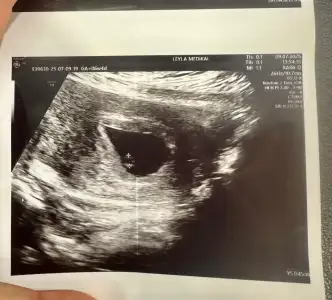

6 haftalik karından ultrasyon tahminde bulunabilir misiniz

Eklentiler

• IMG_20250312_112835.webp

IMG_20250312_112835.webp

31,3 KB · Görüntüleme: 70

• IMG_20250312_094215.webp

IMG_20250312_094215.webp

21,9 KB · Görüntüleme: 58

• IMG_20250312_094132.webp

IMG_20250312_094132.webp

44,2 KB · Görüntüleme: 73